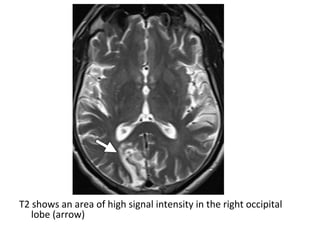

ADC map shows an area of low signal intensity in the right parietooccipital

junction (arrow) , a finding that usually persists for about 1 week , this

area demonstrates high signal intensity at diffusion-weighted imaging (not

shown)

T1 shows an area of low signal intensity (arrow)

T2 shows an area of high signal intensity (arrow)

FLAIR shows an area of high signal intensity (arrow)